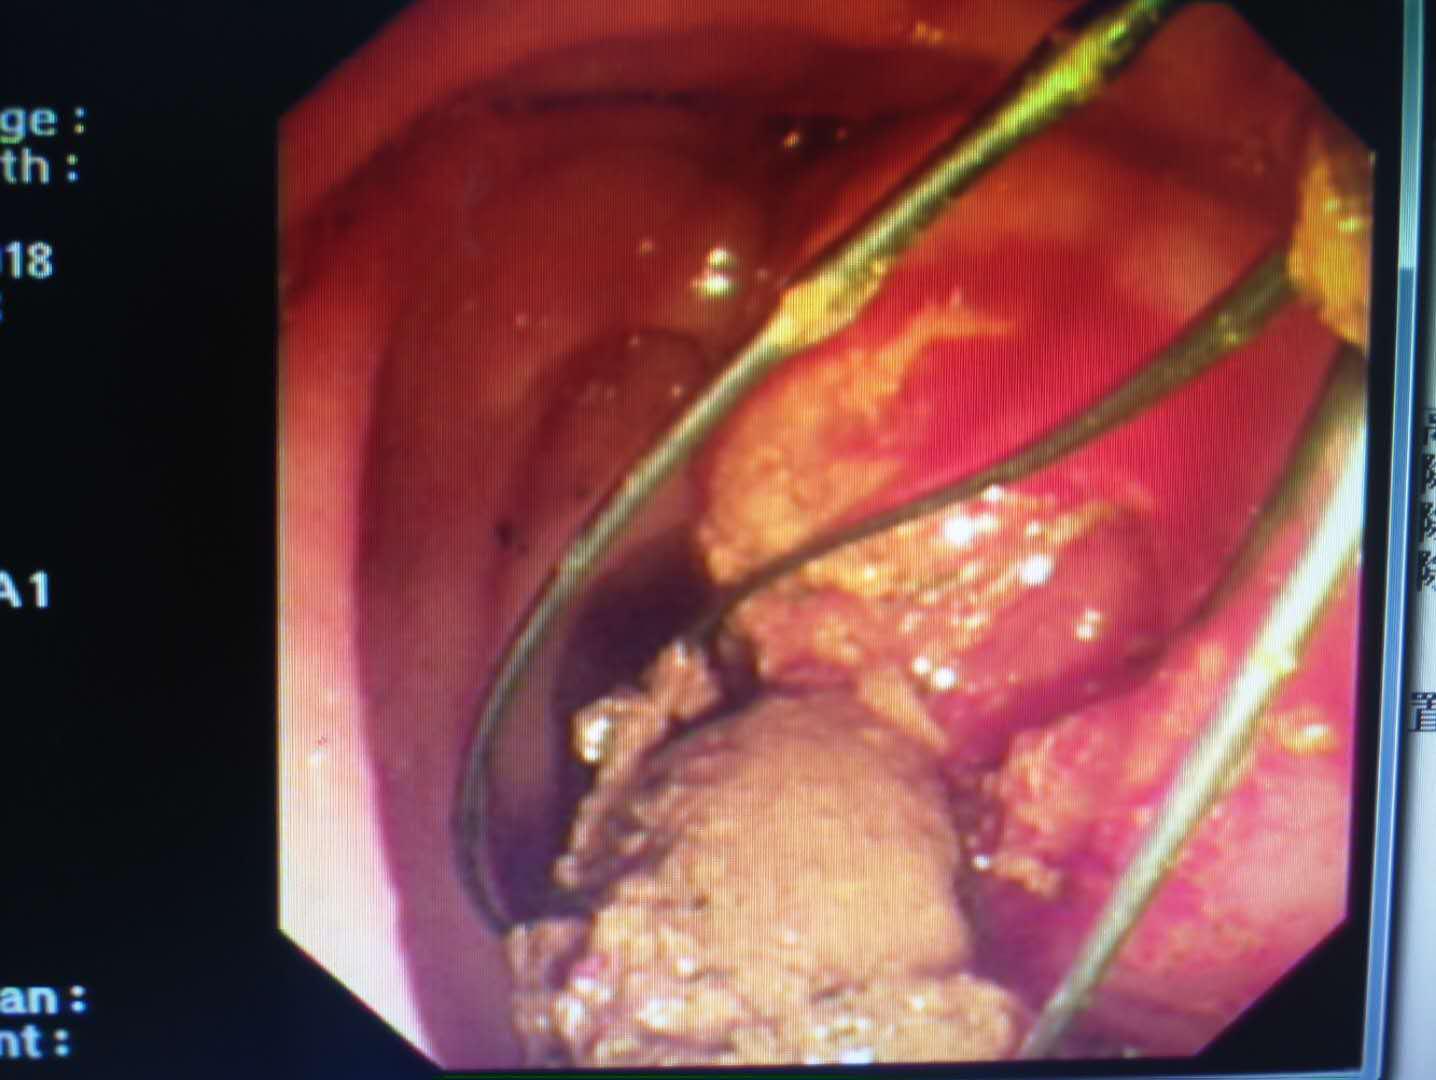

患者梁某,女性,87岁,因“腹痛2月”收住消化内科,诊断为胆总管结石、化脓性胆管炎、冠心病、心房纤颤、高血压2级、脑梗塞、电解质紊乱(低钾血症)。患者入院后伴有发热,最高体温41℃,急性化脓性胆管炎症状急剧加重,生命危在旦夕,一分一秒都在与生命赛跑。以往唯一生还的机会就是开刀手术,但是这位高龄患者很难下手术台;如果保守治疗唯一的结果就是因感染性休克及严重合并症而死亡。就在此时,消化内科主任王宇晖、主治医师曹鹏、白欣与手麻科雷育华主治医师、介入科何彤副主任多学科联合会诊,根据病情迅速制定了最佳手术方案,那就是为患者实行ERCP胆道取石。手麻科迅速为患者实行插管麻醉,密切监护生命体征,介入科配合,由曹鹏医生快速将胆管内的巨大结石顺利取出,迅速解除了胆道梗阻,缓解了患者胆道压力,安全有效缓解了患者的危重病情。

术后第二天,87岁高龄的梁奶奶坐在床上,面容舒缓,满脸笑意,提及到昨日的手术时,她竖起大拇指,激动地说道:“太神奇了,睡一觉手术就完了,身上还没有伤口。”